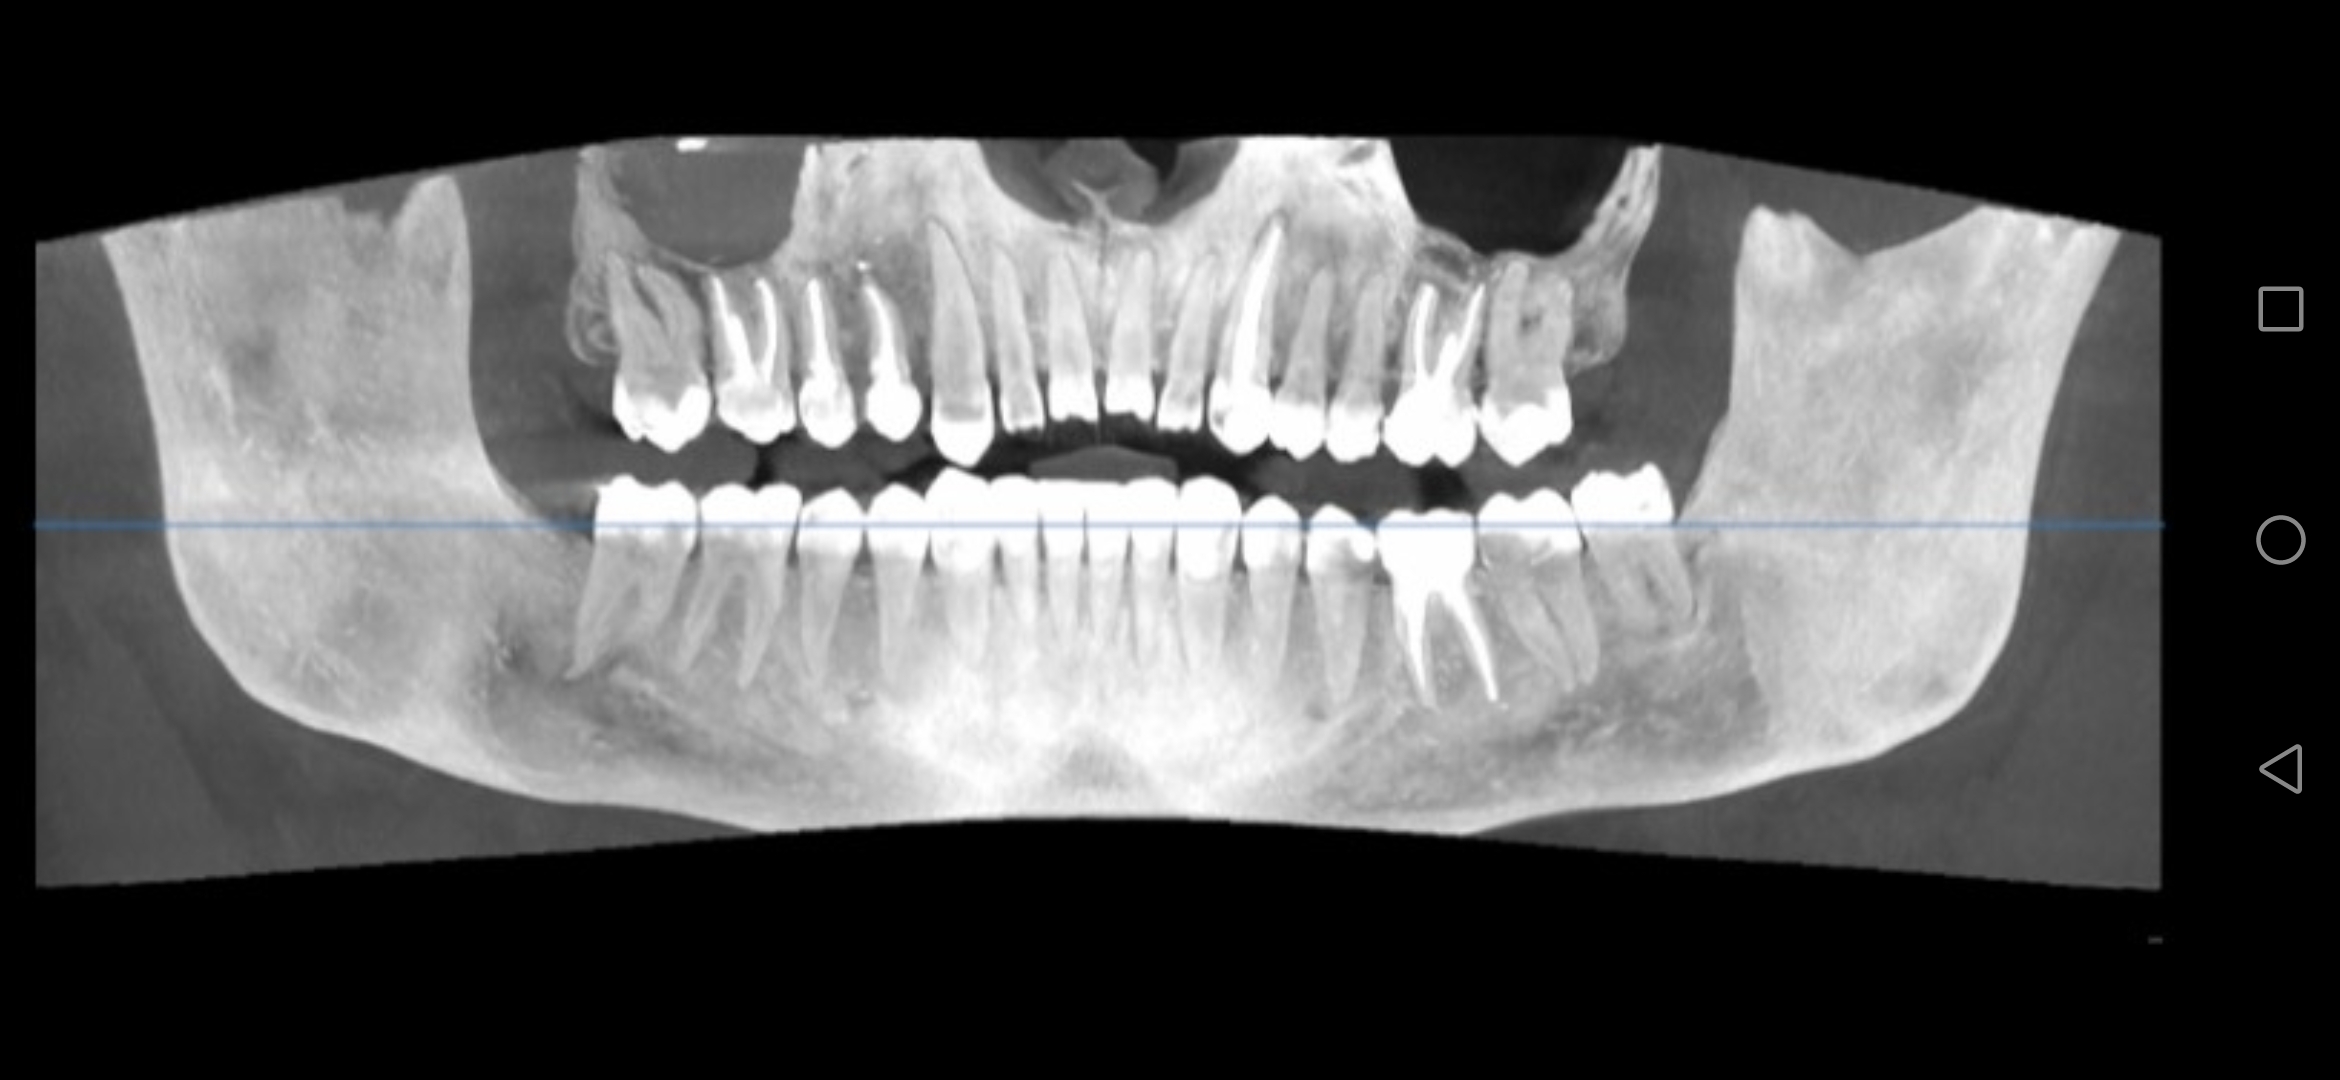

Screenshot20231[...].jpg 414Кб, 2340x1080

2340x1080

Screenshot20231[...].jpg 482Кб, 2340x1080

Боя, я в ахуе, вы в каком веке живёте. Есть такая штука как КЛКТ, стоит копейки, делается 2 минуты. Является золотым стандартном диагностики ЛЮБЫХ зубных пиздецом, там в 3д видно все - кисты, периодонтиты, состояние пазух и тд. Любой приличный врач а) не станет производить серьёзных манипуляций без таких снимков б) спокойно все увидит и распишется где и из за чего у вас болит. Нет бля ходят что-то лечат неизвестно что, не могут определить что и где у них болит, вы ебанутые?